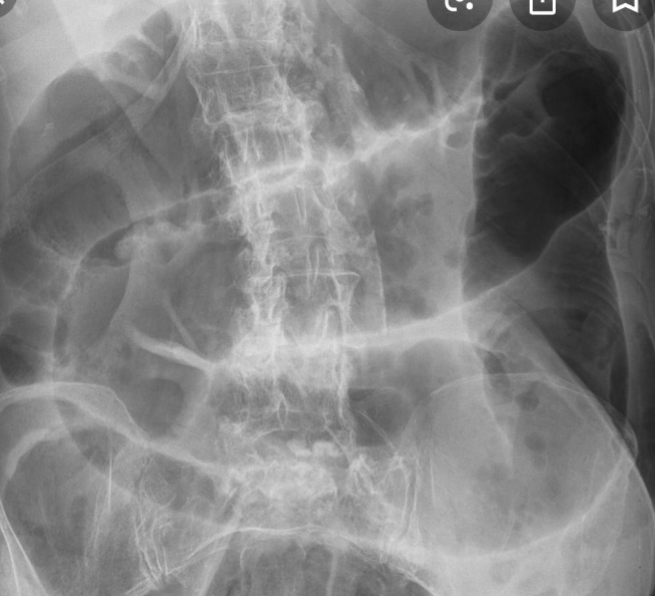

Large bowel obstruction

1- What is imaging technique? X-ray

2- what is your findings? Dilated + obstructive intestine

Mention 4 causes of this condition? Neoplasm, volvulus, polyp, hernia, adhesions, intussusception

Small bowel obstruciton

Q1- Write the name of this imaging and what is your finding?

- plain film air fluid level

- small bowel obstruction with coin sign (valvulae conniventes)

Q2-Write 2 of the possible causes?

- Stricture

- Complicated hernia

Q3-What is your management? concretive treatment

- iv fluid

- nasogastric tube

- observation the pt.

- CT with contras

Q1: Mention (A) type of imaging study, and (B) Your finding. A) Abdominal x-ray/ plain film/ probably supine position

B) Dilated small bowel loops (small intestine obstruction)

Q2: What is the commonest cause of this condition? Adhesions

Q3: Mention 4 important steps in the treatment. NOP, IV fluids, NG tube, pain killers